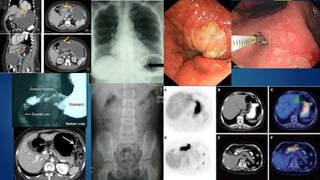

Diagnostic workup

• Upper endoscopy(location and extent of disease)

• Multiple biopsies of the lesion(to obtain a histologic

diagnosis)

• Endoscopic ultrasound(determine the depth of tumor

invasion and the presence of enlarged lymph nodes)

• CXR and CT of the abdomen and pelvis(screening

modalities)

• PET (detecting advanced disease)

• Laboratory investigations(blood cell count, electrolytes, creatinine

level, and liver function tests)

• Laparoscopy(metastasis to the peritoneum and the omentummay)